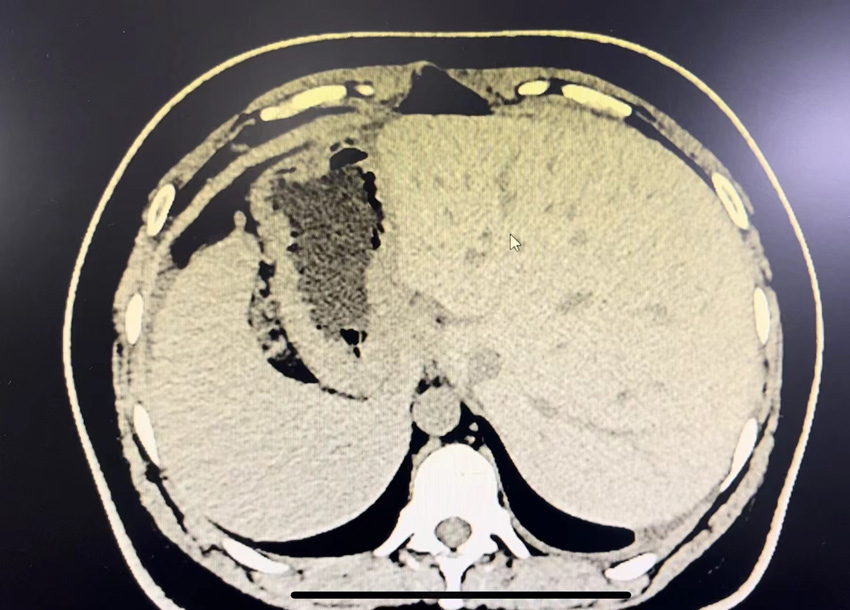

患者內臟反向生長。四川省人民醫院供圖

“鏡面人”是指人的心臟、肝臟、脾臟、膽囊、胰腺、脾臟等器官的位置與正常人完全相反,就像照鏡子一樣,所以又稱為“鏡面人”。醫學上,對“鏡面人”現象的成因還沒有科學定論。目前研究認為,“鏡面人”可能與人體胚胎發育過程中基因突變有關,其發生幾率大約為百萬分之一。